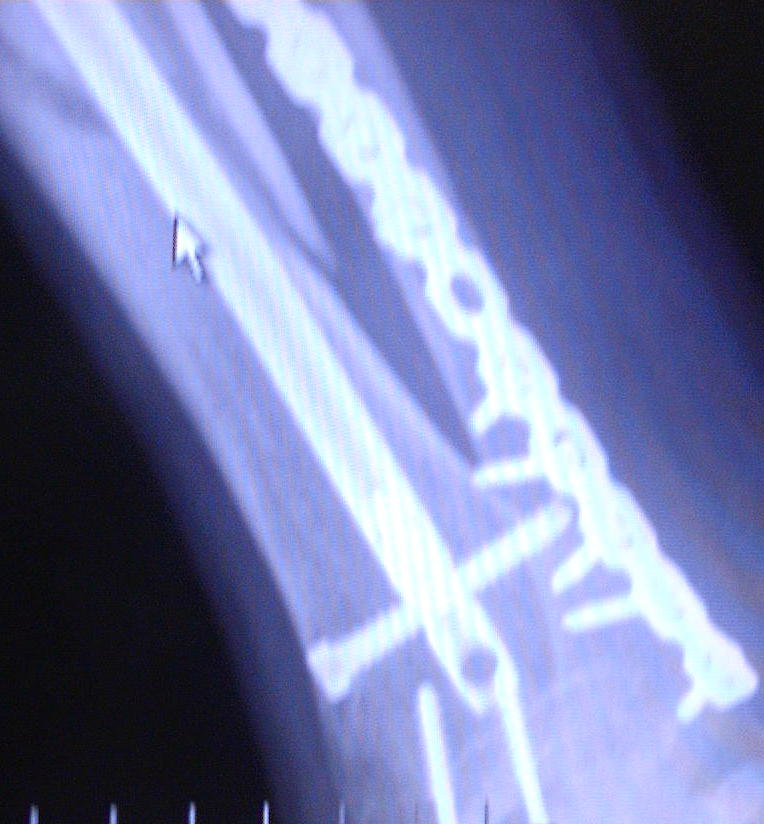

This is Diesel's X-ray's from 9-30-04. He broke hiz tibula on June 21, 2004 doing a 12 o'clock wheelie. Clutch slipped and he flipped over the handle bars and landed ALL hiz weight on hiz right leg causing it to snap.

He just got hiz 3rd cast removed and found out that the bone is not progressing. He now has an walking cast on with a bone stimulator (to maximize circulation to that area) which he will most likely have for the next 6 months. As you can see in the X-Ray's he has a metal plate on the anterior side of hiz ankle where he broke it in 2 places. You can see where the tibula broke and how it is not healing. He has 13 screws and a titanium rod throughout the tibula. Price you pay for being a Stunter!

He just got hiz 3rd cast removed and found out that the bone is not progressing. He now has an walking cast on with a bone stimulator (to maximize circulation to that area) which he will most likely have for the next 6 months. As you can see in the X-Ray's he has a metal plate on the anterior side of hiz ankle where he broke it in 2 places. You can see where the tibula broke and how it is not healing. He has 13 screws and a titanium rod throughout the tibula. Price you pay for being a Stunter! "INSANE STUNTERZ"